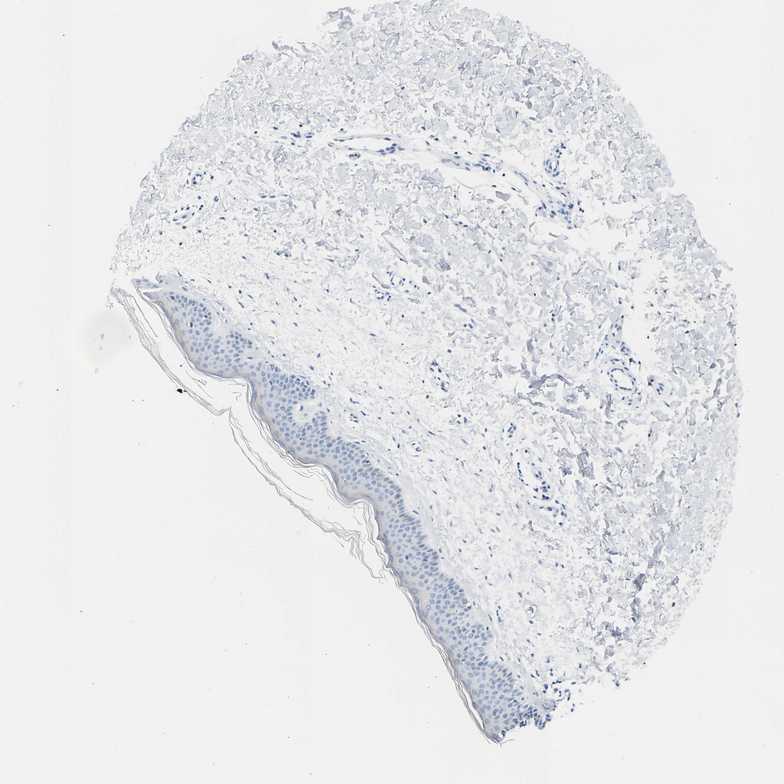

SKIN 2 - Antibody stainingi

Antibody staining in the annotated cell types in the current human tissue is reported as not detected, low, medium, or high, based on conventional immunohistochemistry profiling in selected tissues. This score is based on the combination of the staining intensity and fraction of stained cells.

Each image is clickable and will lead to virtual microscopy that enables deeper exploration of all samples and also displays staining intensity scores, fraction scores and subcellular localization as well as patient and tissue information for each sample.

Antibody HPA026813Antibody CAB020824

Epidermal cells Not detectedLow